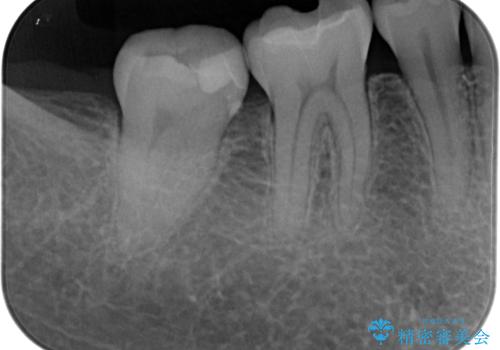

- 右下が黒くなってるとのことで来院された患者様です。レントゲン撮影により虫歯を認め、神経の反応の試験を行い正常な結果を得られたので、セラミックインレーによる修復治療を行っていくことにしました。

拡大鏡視野下で虫歯の除去を行い、セラミックインレーに適した形に整えました。

歯と歯茎の間に圧排糸と言われる糸を入れてシリコーン印象材にて精密な型どりをしました。

セラミックインレーの装着時には、唾液の侵入を防ぐために、ラバーダム防湿を行いました。